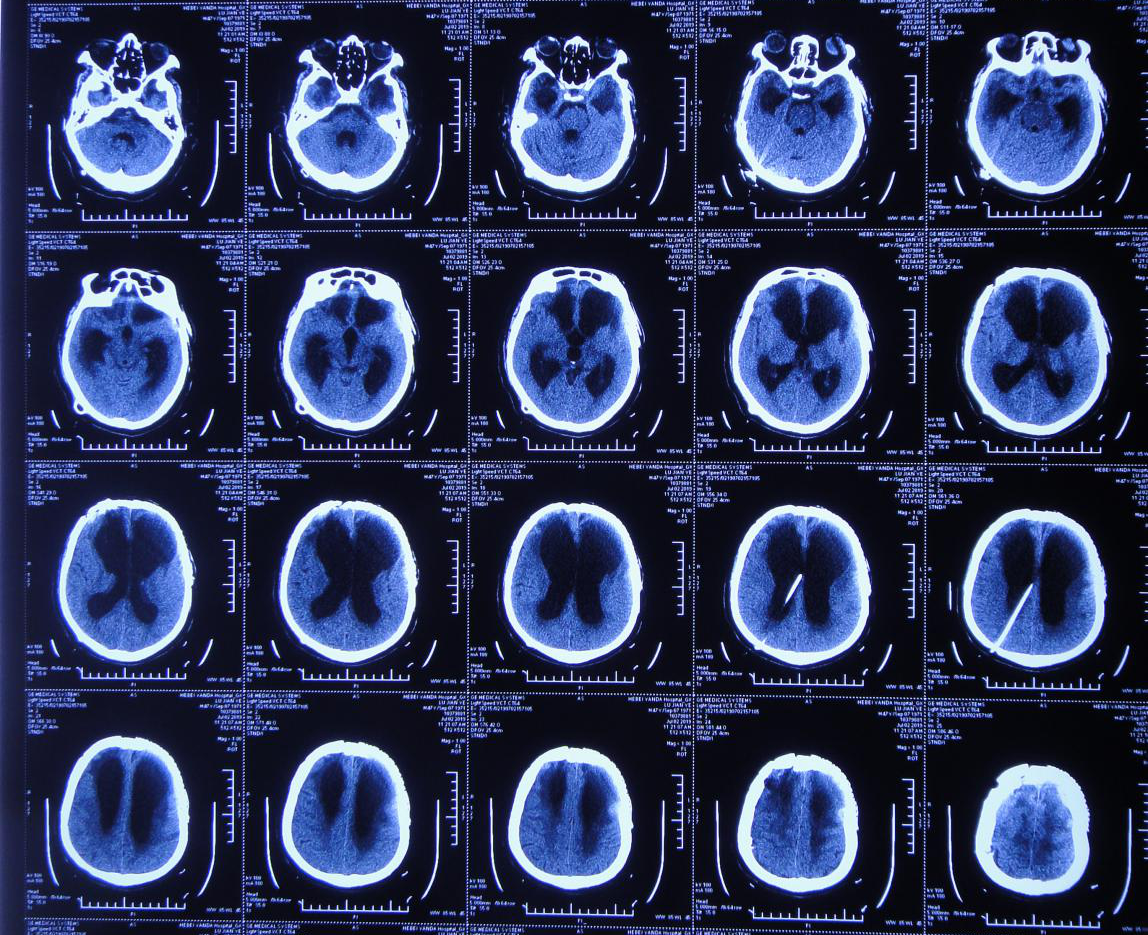

额叶ct

突发头痛入院,神志清醒,肢体活动好,入院头颅cta示左额叶脑出血,左侧

体检发现左侧额叶不规则稍高密度影,ct值约45hu,无占位效应,无明显

于当地医院行ct显示额叶出血

入院后复查ct

第5日颅脑ct

右侧额叶脑出血(头颅ct)

平扫左额叶大片状低密度水肿

日复查ct示枕部血肿基本清除,存留骨桥下血块,左额叶挫裂伤并血肿形成

外院头部ct提示右侧额叶高密度信号影,考虑脑膜瘤可能性大?

行头颅ct(片子遗失)检查示双额叶脑挫裂伤,少量出血

患儿刚住院时的ct检查,右额顶叶少量硬膜下血肿

颅脑ct示左侧颞叶高密度影,考虑血肿

ct:左侧额 颞叶 基底节区脑内血肿